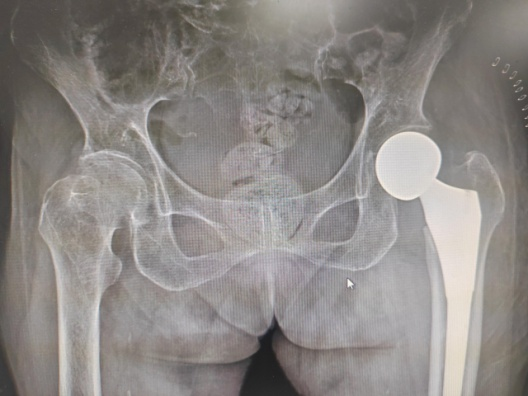

近日,近100歲高壽的潘奶奶,在家上廁所時(shí)不慎摔倒,導緻左股骨頸骨折(頭下型),其家屬急忙將(jiāng)潘奶奶送至惠州六院急診科。經(jīng)急診醫生初步評估後(hòu)轉送至惠州六院關節外科、運動醫學(xué)科病區,經(jīng)過(guò)術前檢查發(fā)現,潘奶奶左股骨頸骨折,又有重度骨質疏松症、雙側髋關節退行性變等20項病症。患者高齡,基礎疾病多,手術風險高。

8月15日,由關節外科、運動醫學(xué)科主任餘金勝主刀,帶領手術團隊成(chéng)功進(jìn)行左側人工股骨頭置換術,術中用時(shí)不到30分鍾成(chéng)功置入髋關節假體,整個手術用時(shí)約80分鍾,術中仔細止血,術中無需輸血。